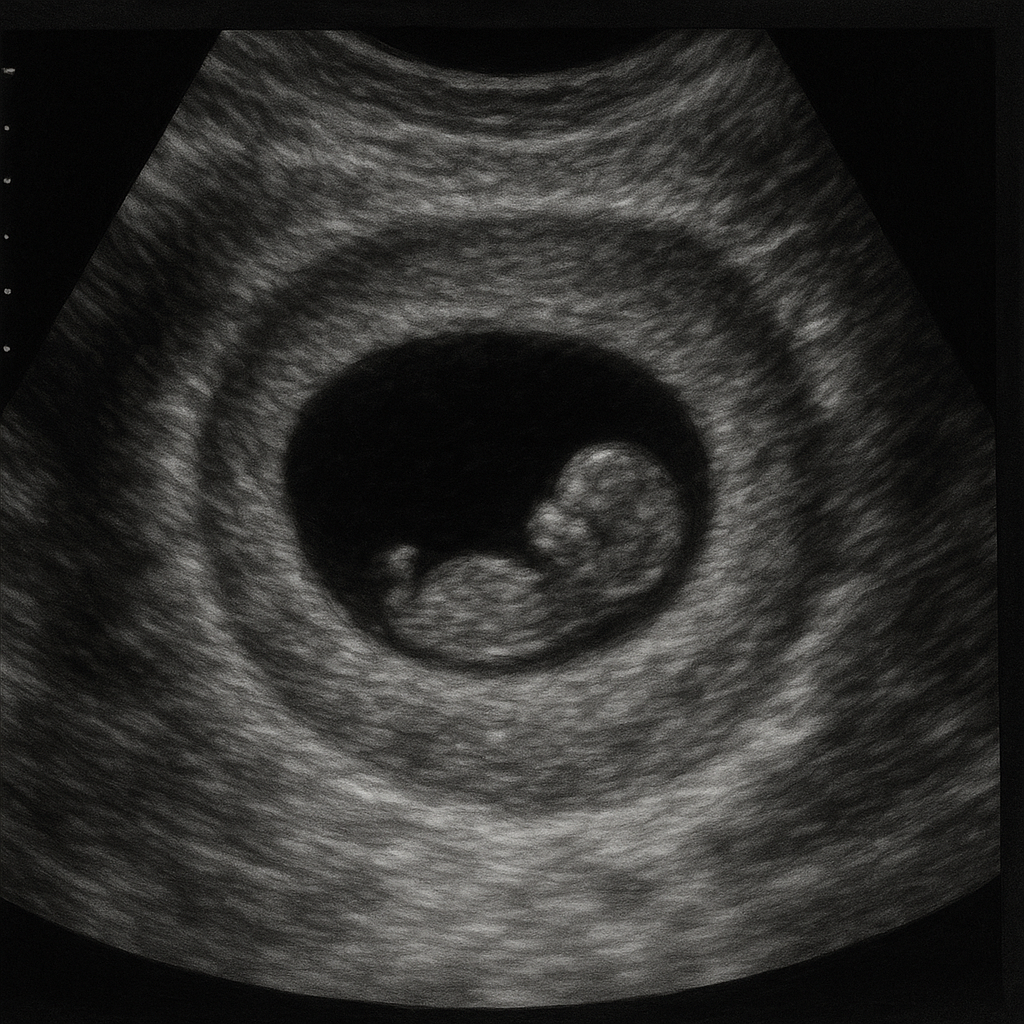

🖥 3. 초음파 검사

- 복부 또는 질 초음파로 임신 여부 및 위치 확인

- 너무 초기는 보이지 않을 수도 있어요

Q. 아기 심장 소리는 언제 들을 수 있나요?

A. 임신 6~7주 경 질식 초음파에서 심장박동을 확인할 수 있습니다. (대한산부인과학회 자료 기준)